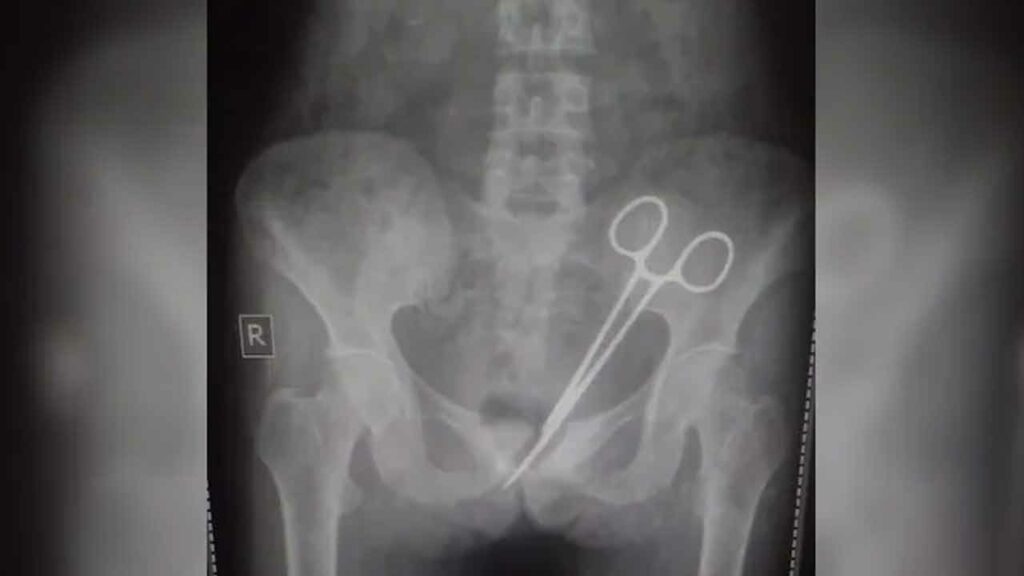

కడుపు నొప్పి మరింత తీవ్రం కావడంతో చేసేదేమీ లేక ఈ ఏడాది అక్టోబర్ 8న సర్ తుటుబ్ నమ్గ్యల్ మెమోరియల్ ఆస్పత్రికి ఆమెను తీసుకెళ్లారు. అక్కడ బాధిత మహిళకు స్కానింగ్ నిర్వహించగా, పొత్తి కడుపులో కత్తెర( Scissors ) ఉన్నట్లు వైద్యులు( Doctors ) నిర్ధారించారు. దీంతో ఆవిడకు సర్జరీ( Surgery ) నిర్వహించి కత్తెరను తొలగించారు.

అయితే ఆమెకు 12 ఏండ్ల క్రితం అపెండిక్స్( Appendix ) నొప్పి వచ్చింది. దీంతో సర్ తుటుబ్ నమ్గ్యల్ మెమోరియల్ ఆస్పత్రి వెళ్లగా, వైద్యులు శస్త్ర చికిత్స నిర్వహించారు. సర్జరీ అనంతరం ఆమె పొత్తి కడుపులోనే కత్తెర మరిచి కుట్లు వేశారు. ఇక అప్పట్నుంచి ఇప్పటి వరకు ఆమె కడుపు నొప్పితో బాధపడుతూనే ఉంది. చివరకు ఆ కత్తెరను తొలగించారు వైద్యులు. ప్రస్తుతం బాధిత మహిళ ఆరోగ్య పరిస్థితి నిలకడగా ఉందని వైద్యులు తెలిపారు.